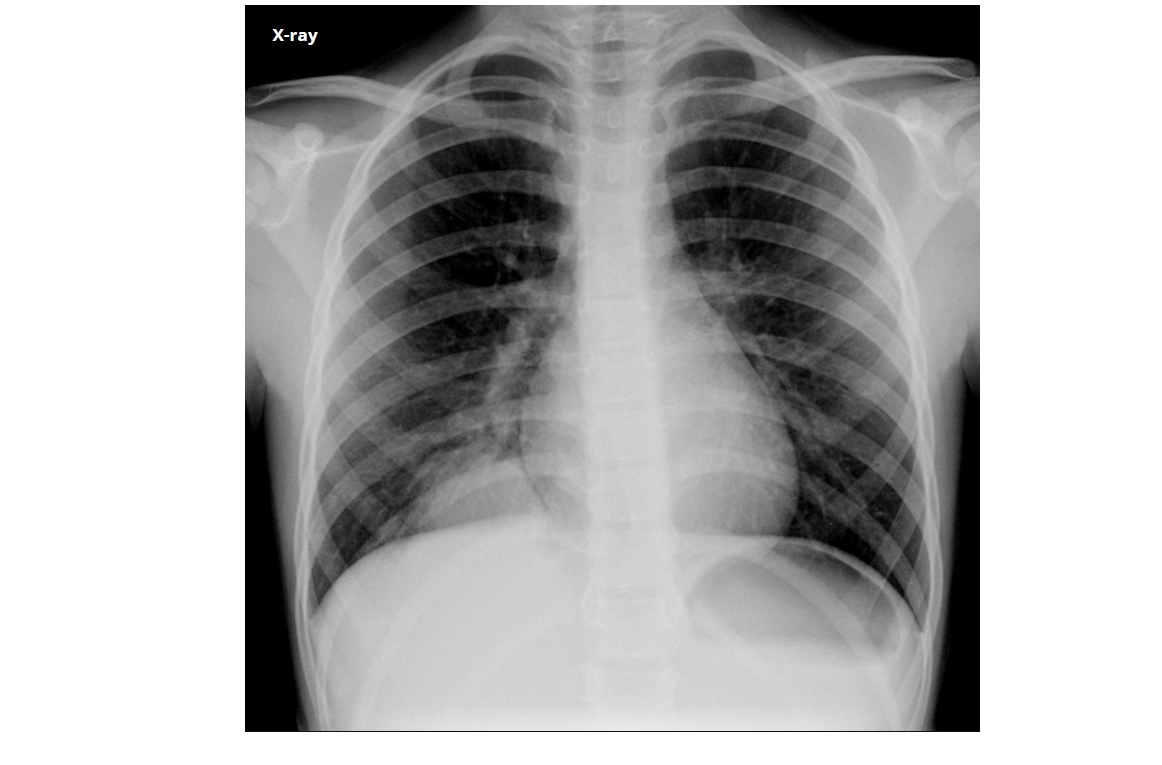

CXR

Reticular or reticulonodular opacities

Subpleural/peripheral; mid and lower lung zones

Macrocystic Honeycombing (strongest predictor)

Basilar predominant

Traction bronchiectasis

Subpleural reticulations

smoking association

Causes

- connective tissue disease such as RA

- asbestosis

- Drugs (amidorane, nitrofurantoin, methotrexate)

- IPF (diagnosis of exclusion)